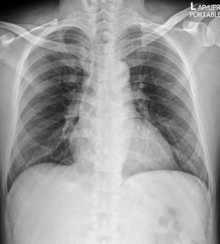

Radiographic findings

พบความผิดปกติจากภาพถ่ายรังสีทรวงอกในวันแรกที่รับไว้ในโรงพยาบาล 66% โดยส่วนใหญ่ที่พบเป็น bilateral peripheral opacities/consolidations (รูปที่ 1) มีส่วนน้อยที่เป็น unilateral involvement (รูปที่ 2) บางรายพบลักษณะของ focal opacities ทำให้ดูคล้ายเป็น nodule หรือ mass (รูปที่ 3) และพบ pleural effusion (รูปที่ 4) เพียง 3 รายเท่านั้น ได้ทำการตรวจ CT scan ไป 4 ราย ซึ่งพบว่ามีความไวในการตรวจพบความผิดปกติได้เพิ่มขึ้น

รูปที่ 1. แสดงภาพถ่ายรังสีทรวงอกธรรมดา (ซ้ายมือ) และคอมพิวเตอร์ (ขวามือ) ของผู้ป่วยวันที่ 21 หลังเริ่มมีอาการติดเชื้อโควิด-19 พบลักษณะ bilateral peripheral opacities/consolidations